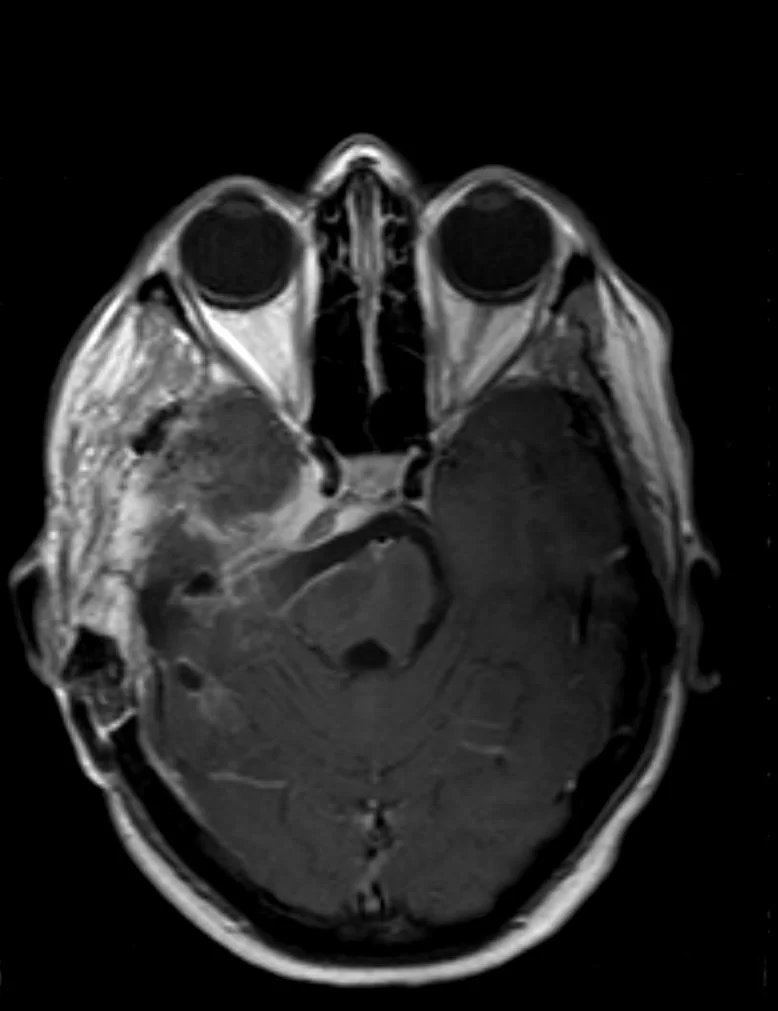

Η μετεγχειρητική αξονική τομογραφία εγκεφάλου δείχνει σημαντική μείωση του όγκου, με ελάχιστα υπολειμματικά στοιχεία στην περιοχή του σηραγγώδους κόλπου δεξιά. Η ιστολογική εξέταση ανέδειξε μηνιγγίωμα (WHO I).

Μετεγχειρητικά η ασθενής παρουσίασε επιδείνωση της ημιπάρεσης αριστερά, περαιτέρω έκπτωση της ακοής και πάρεση του τροχιλιακού νεύρου. Περίπου 12 μήνες μετά το χειρουργείο η ημιπάρεση είχε αποκατασταθεί στα προεγχειρητικά επίπεδα ενώ η πάρεση του τροχιλιακού και η έκπτωση της ακοής παρέμενε.